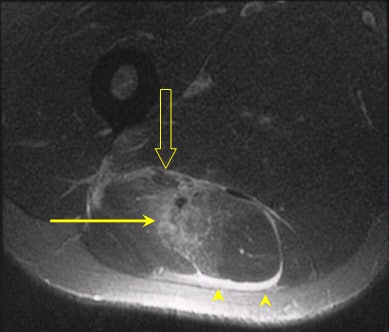

| Axial images of the same patient as above demonstrate again the tear at the musculotendinous junction (arrow). Further to this, a rim of hyperintensity is noted around the fascial layer of the muscle boundary (arrowheads). The sciatic nerve is identified anterior to the muscle, however not in contact with the extravasated fluid (open arrow). The corresponding sonogram was also abnormal, with the player missing competition for three weeks. |

MR imaging is noted to be more sensitive in the detection of soft-tissue injury compared to ultrasound, particularly in the setting of edema without visible macroscopic disruption. MRI scans demonstrated edema and hemorrhage as bright signal on proton-density sequences, which acts as a direct contrast with the gray isointense signal of muscle. This accounts for the high sensitivity of this modality, as well as the benefits of multiplanar capability (also a benefit of sonography).

MRI also probably depicts fluid around the sciatic nerve more accurately, which may account for neural tension and radiculopathy following injury. This has been postulated to be a cause of recurrent injury following injury to the HMC, as well as a prolonged rehabilitation period.